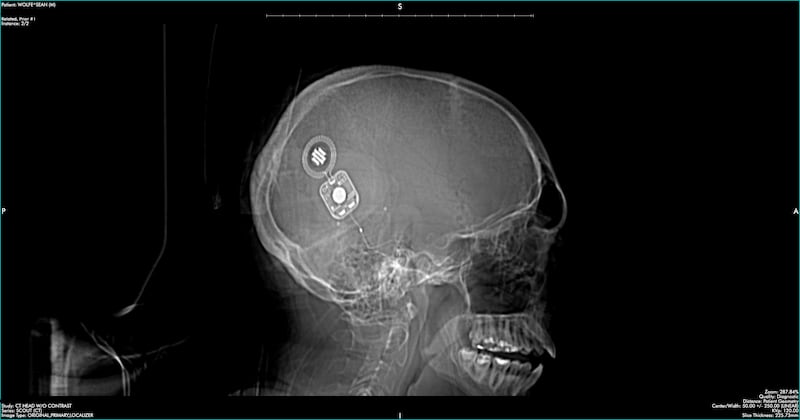

His two remixes of the Chicago band Still Machines’ song “Echoes Within” are directly inspired by his experience with a cochlear implant, or CI—a surgically implanted prosthesis he received in 2024 after losing most of the hearing in his right ear.

“There’s basically a wire with a bunch of electrodes, and each electrode only triggers a certain frequency band,” Wolfe explains. “The in-between sounds are kind of weird.”

After learning that removing the tumor would destroy what was left of his hearing in that ear, Wolfe opted for the implant. Relearning how to hear through a cochlear implant is a difficult and intensive process, but he’s never felt more driven to make music.